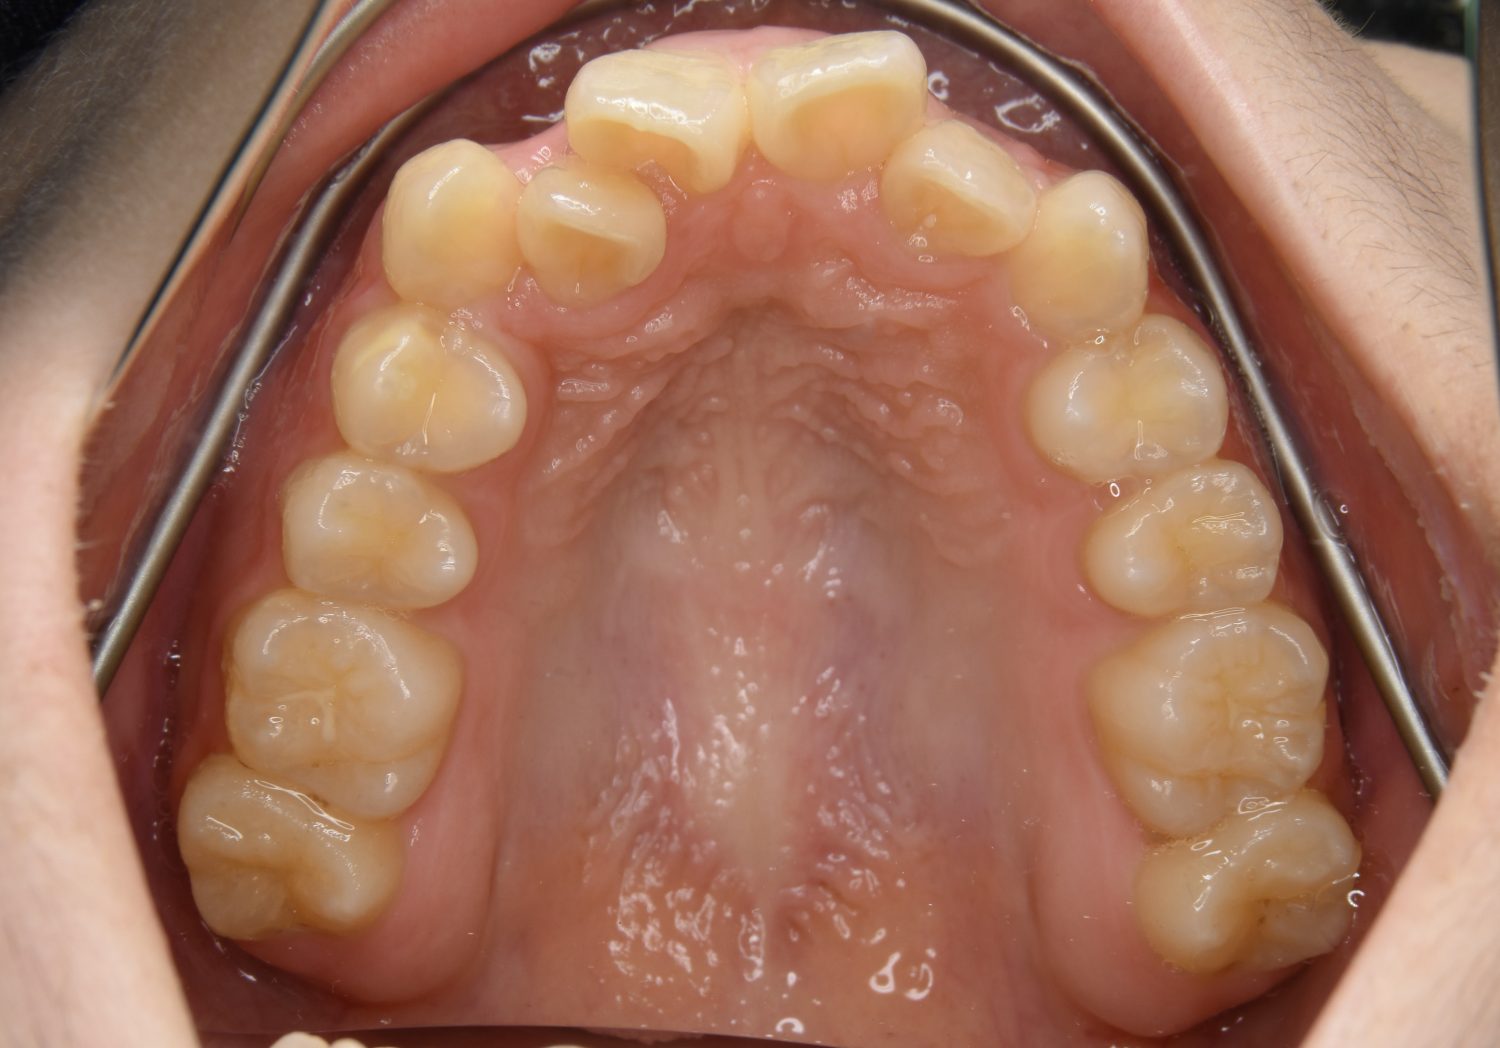

叢生の症例紹介①

Before

After

主訴

前歯のガタガタが気になる。

治療内容

上顎左側第一小臼歯を抜歯し、アライナー(インビザライン)にて治療を行いました。

左上の側切歯が完全に内側に入り込んでいる状態でした。左上の第一小臼歯のみ抜歯を行い治療を行うことで機能面および審美面を改善しました。